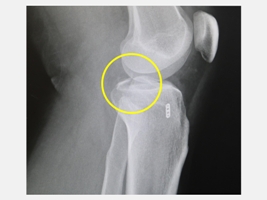

台中一位28歲黃先生在騎機車上班途中發生車禍,左腳膝蓋又腫又痛,不只躺在地上爬不起來,甚至連膝蓋彎曲都有困難,由救護車送到仁愛長庚合作聯盟醫院(大里仁愛醫院)的急診室,X光檢查發現其左腳膝關節骨折,經進一步電腦斷層掃描後顯示是脛骨後十字韌帶撕脫性骨折(posterior cruciate ligament avulsion fracture)。運動醫學中心徐振恆醫師安排微創關節鏡輔助復位固定手術後,黃先生隔天就開始下床走路,並進行復健運動,2個月之後已經回到正常生活。

徐振恆醫師指出,由於台灣機車族眾多,每天交通事故頻繁,除了常見擦傷、骨折外,膝關節的十字韌帶受傷也屢見不鮮。黃先生的後十字韌帶撕脫性骨折(即後十字韌帶連帶一小塊骨折塊從脛骨上被拉起),最常見於機車車禍,原因是在跌倒時膝蓋彎曲脛骨受到直接向後的衝擊力所造成。黃先生在事故發生後膝蓋不但疼痛、腫脹,還感覺膝蓋不穩,即使勉強拿拐杖行走,膝關節也沒有力氣支撐,這種傷勢不但可能造成膝關節不穩,若未即時和正確治療,還可能導致日後膝關節退化與功能障礙。